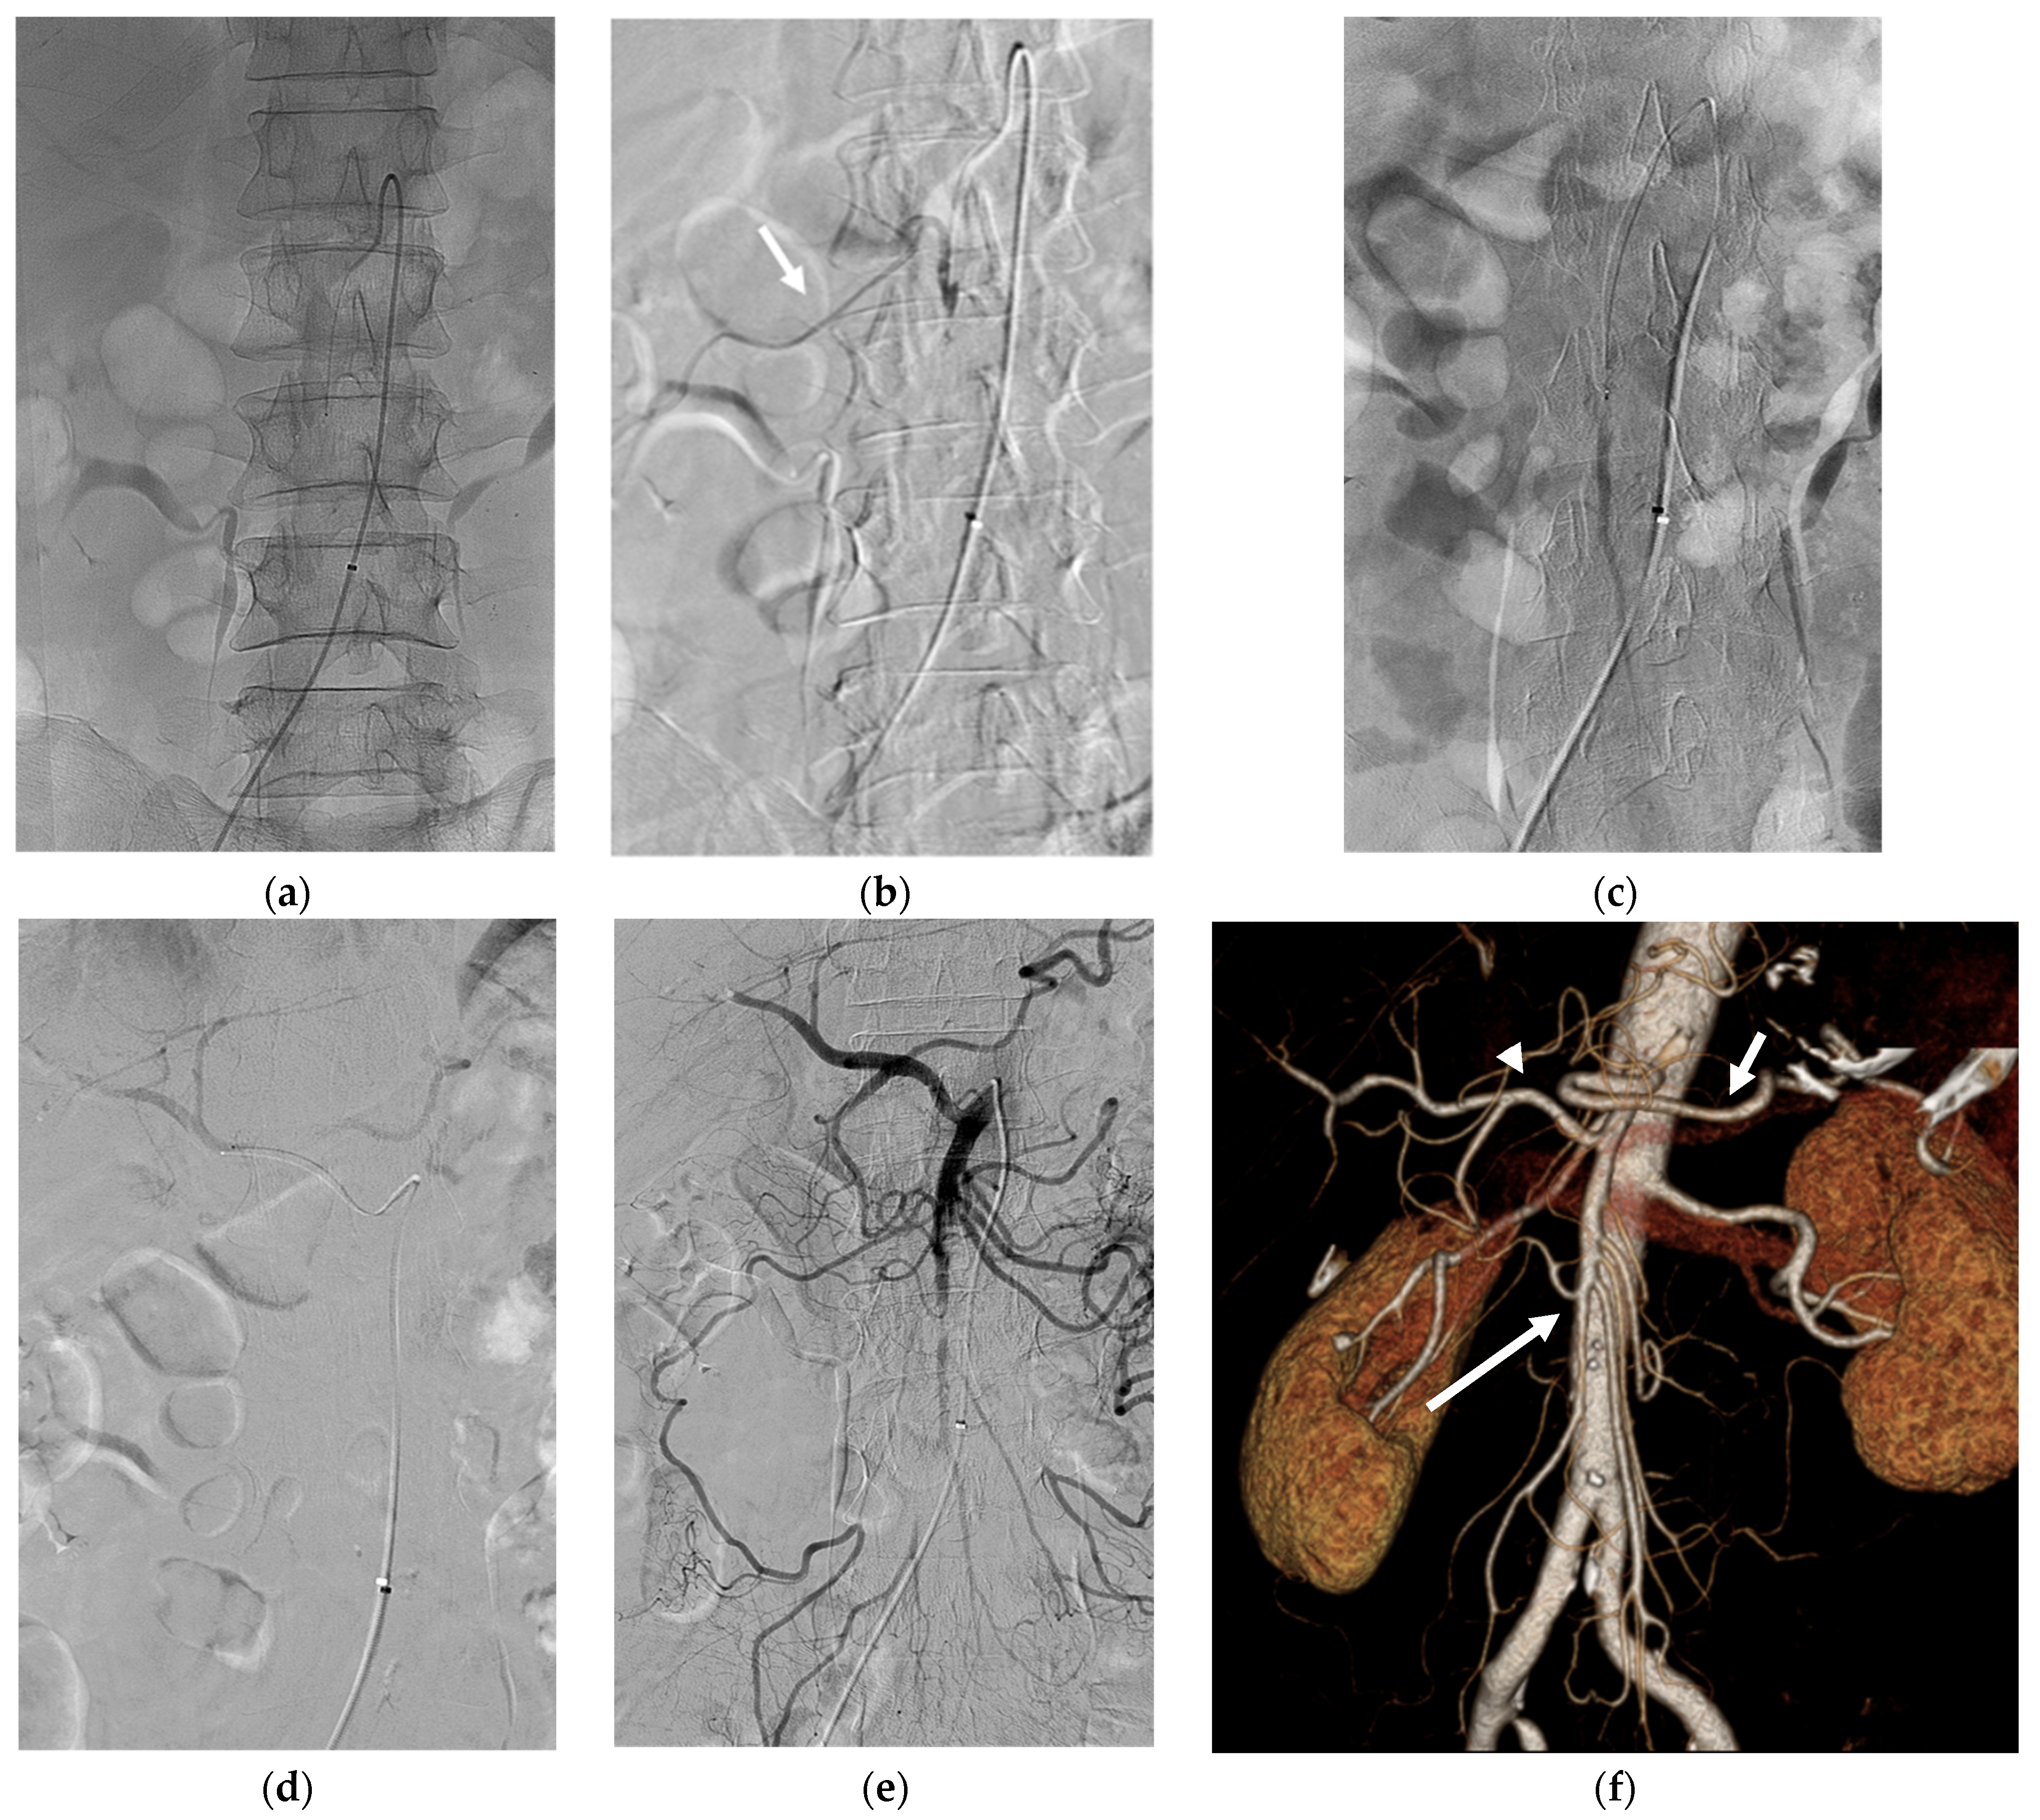

A 1.9 Fr microcatheter was advanced immediately in front of the SMA occlusion site, and 0.5 mg of rtPA (5 mL solution) was injected for 10 min. After the injection, angiography revealed partial recanalization of right colic flow. The microcatheter was then advanced into the middle and distal branches of the SMA, and rtPA (0.5 mg) was injected again for 10 min. Additionally, the CHA and splenic artery were selectively catheterized using a 5 Fr RH catheter and a microcatheter. Subsequently, 0.5 mg of rtPA was injected into each artery in front of the occluded site. The final angiogram revealed near-complete revascularization of the SMA (Figure 3). To avoid bleeding complications, no additional rtPA was administered.

After the procedure, the patient was admitted to the intensive care unit and was administered continuous intravenous heparin infusion. No immediate major or minor postoperative complications occurred. After two days, contrast-enhanced CT revealed successful recanalization of the SMA and CHA occlusion without bowel ischemia or active bleeding. Eight days after thrombolysis, the patient was discharged and subsequently treated with warfarin for atrial fibrillation.

Figure 3. (a) The 1.9Fr microcatheter was advanced in front of the SMA occlusion site and 0.5 mg of rtPA was injected for 10 min. (b) After the injection, angiography revealed partial recanalization of right colic flow (arrow). (c) The microcatheter was then advanced into the middle and distal SMA and 0.5 mg of rtPA was injected for 10 min. (d) The CHA was also selectively catheterized using the microcatheter and 0.5 mg of rtPA was injected for 10 min. (e) Final angiography revealed near total recanalization of SMA and its branches. (f) After 2 days, follow-up three-dimensional volume-rendered image of abdominal CT angiography revealed successful recanalization of the SMA (long arrow), the CHA (arrowhead), and the splenic artery (short arrow).